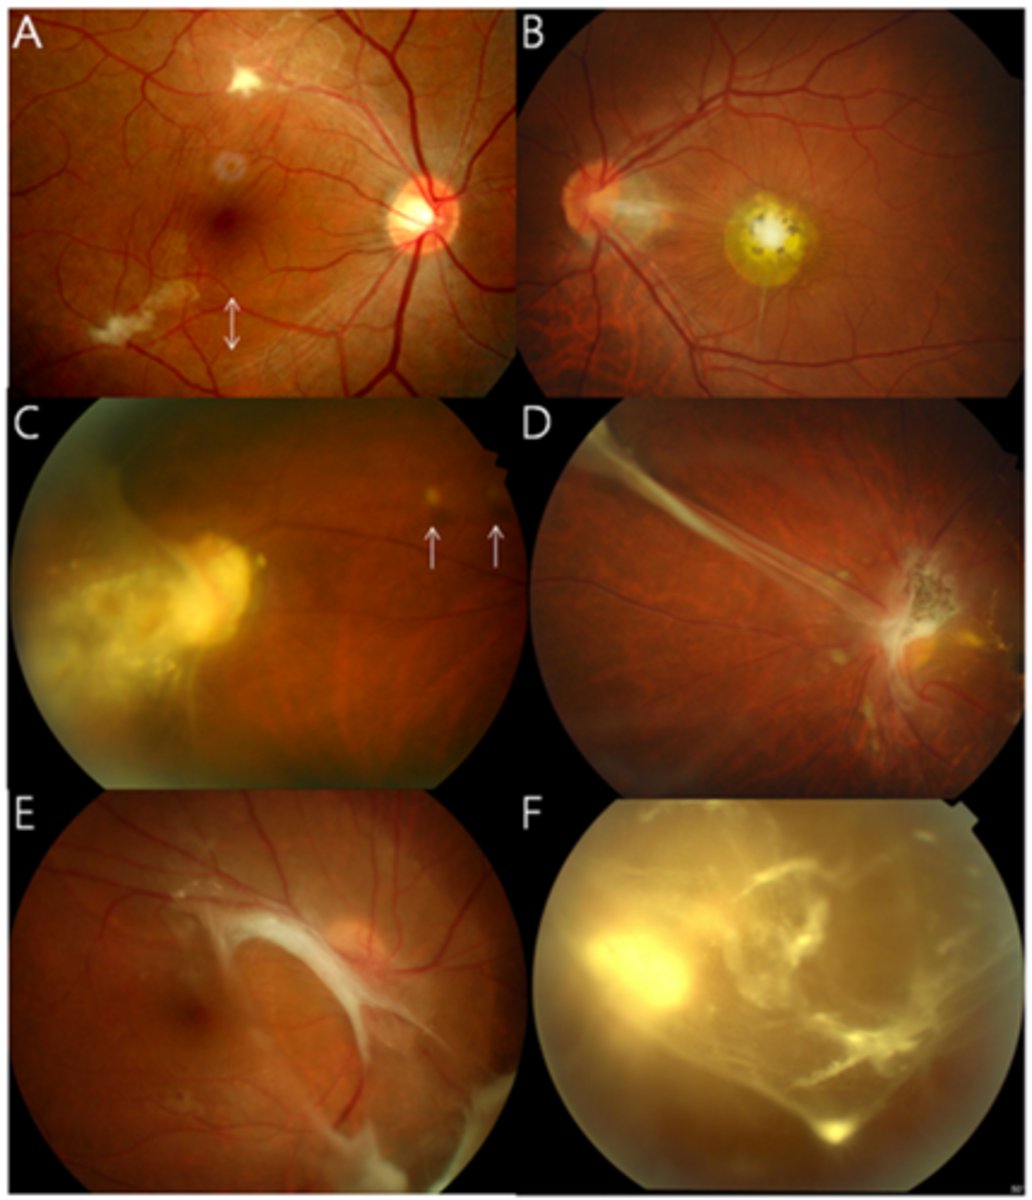

What finding of toxoplasmosis is seen in A/B?

retinitis turns into hazy scar with nerve pallor

What finding of toxoplasmosis is seen in C/D?

scarring overtime with VA loss/scotoma

What is seen in toxoplasmosis with OCT?

acute = retinitis = inflam, thickening of layers

acute = vitritis = dots and haze vitreous

chronic = necrotizing atrophy = scarring, thinning

What findings of toxoplasmosis are seen here?

retinal vasculitis

exudative scar

focal, hazy vitritis and retinitis

What findings of toxoplasmosis are seen here?

latent scars